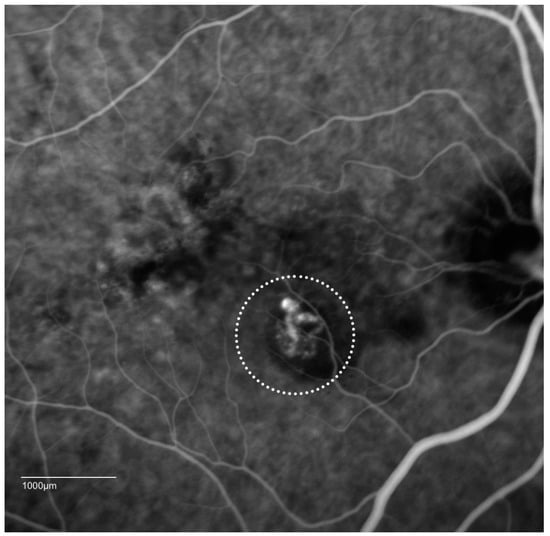

- Cheung, C.M.; Lai, T.Y.; Chen, S.J.; Chong, V.; Lee, W.K.; Htoon, H.; Ng, W.Y.; Ogura, Y.; Wong, T.Y. Understanding indocyanine green angiography in polypoidal choroidal vasculopathy: The group experience with digital fundus photography and confocal scanning laser ophthalmoscopy. Retina 2014, 34, 2397–2406. [Google Scholar] [CrossRef] [PubMed]

- Srour, M.; Querques, G.; Semoun, O.; El Ameen, A.; Miere, A.; Sikorav, A.; Zambrowski, O.; Souied, E.H. Optical coherence tomography angiography characteristics of polypoidal choroidal vasculopathy. Br. J. Ophthalmol. 2016, 100, 1489–1493. [Google Scholar] [CrossRef] [PubMed]